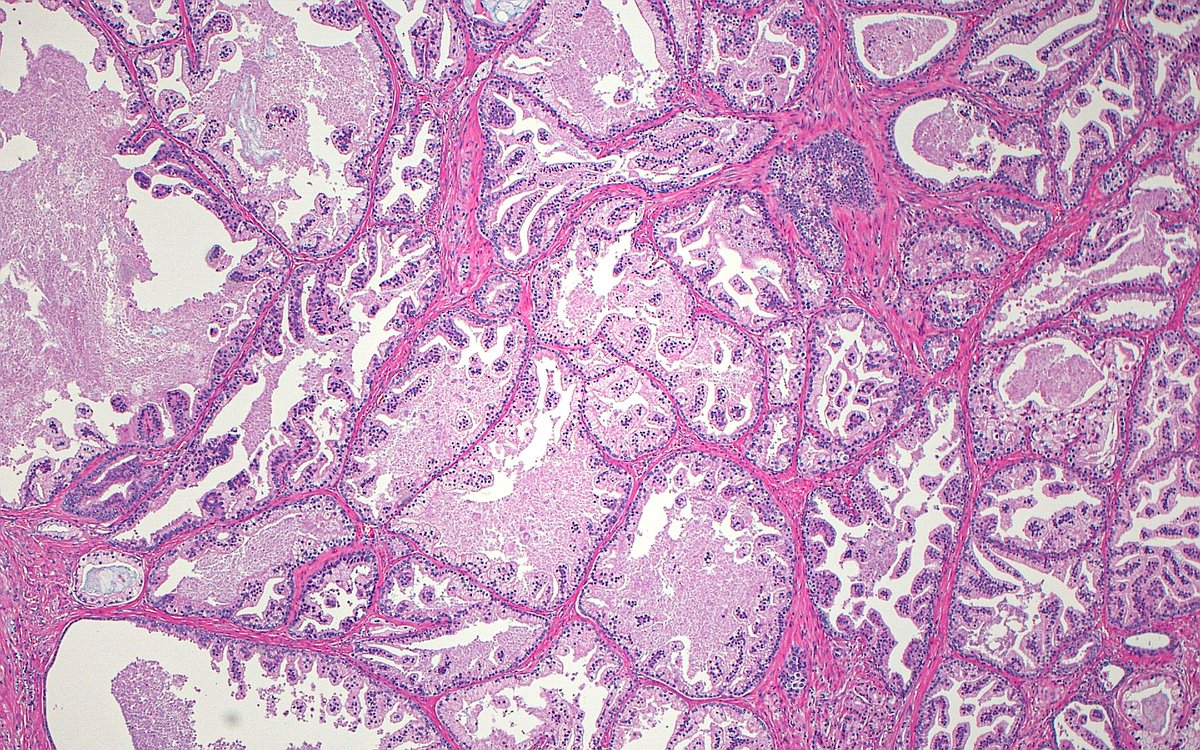

Prostate cancer...or...benign prostatic hyperplasia?

➡️Answer: Prostate cancer, pseudohyperplastic

(One clue: nucleoli in the high mag image!)

#GUpath #pathology #prostate #oncology #urology